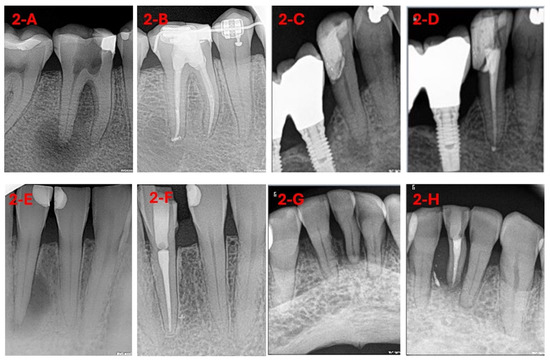

3.1. Sample Selection

3.2. Intervention Procedure